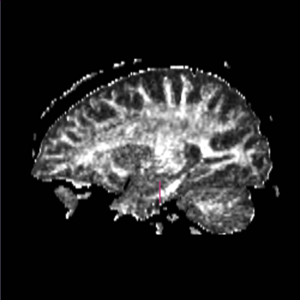

Boundaries for the ROI's, mainly using FA maps & color by orientation, followed by the color coding of the labelmaps.

FornixROI 1) on Coronal view, the first slice where the middle cerebellar peduncles are present ROI 2) posterior to ROI 1; large blobs drawn on coronal view where the middle cerebellar peduncle is clearly connected at bottom of slice